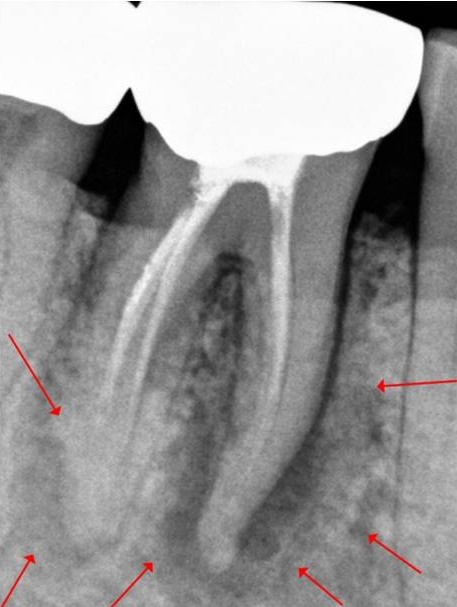

- 치료한 지 오래된 치아라 치근이 파절되어 있고 치근 주위 치조골 상실이 심함 (많이 부어있음)

엑스레이상 #46 치아 주위 치조골은 모두 소실되었고 즉시 임플란트 치료를 하기에도 곤란한 상태였습니다.